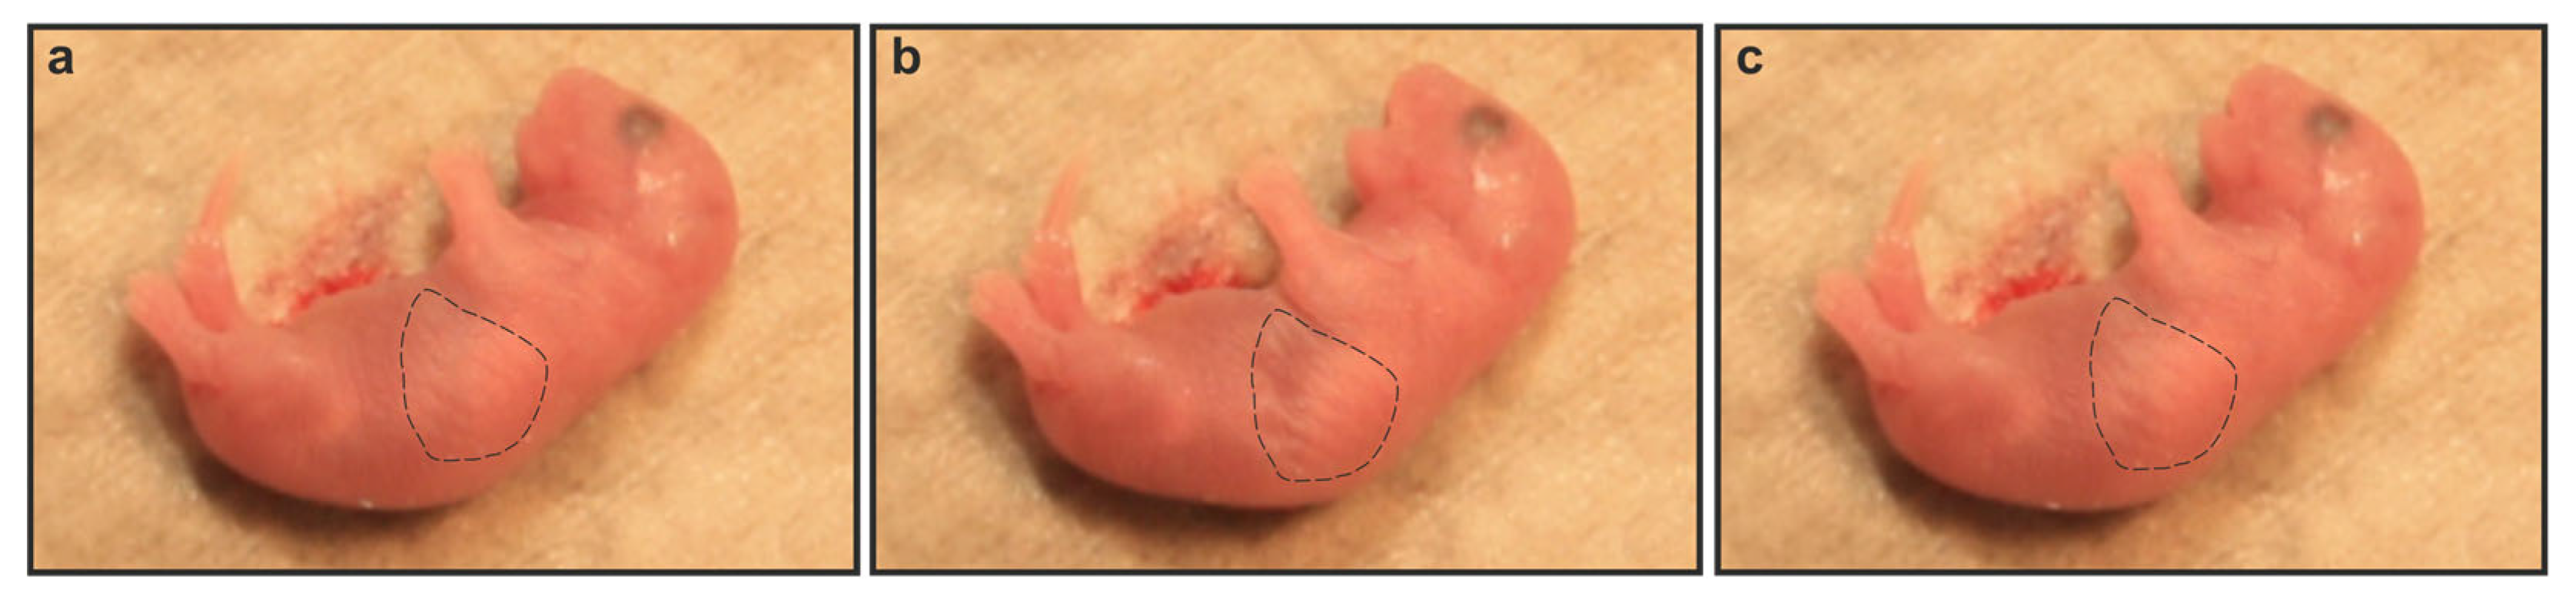

2.2. Gnai2-Deficiency Results in Lung Dysfunction in a Subset of Mice

2.4. Secreted Alveolar Surfactant Fails to Properly Unfold in Deceased Newborn Gnai2-Deficiency Mice